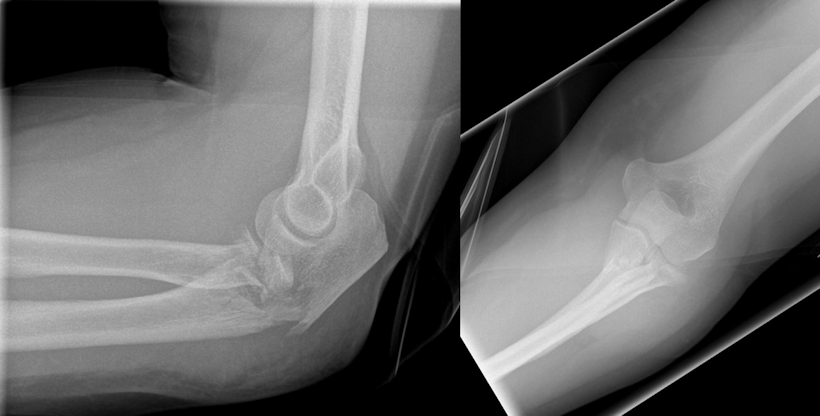

Osteosynthesis of the ulna was performed using a proximally contoured 3.5 mm LCP (locking compression plate) or precontoured 3.5 mm LCP Olecranon Plate (both Synthes GmbH, Umkirch, Germany) applied to the posterior surface of the ulna in dynamic compression mode (Figure 1 [Fig. 1], Figure 2 [Fig. 2], Figure 3 [Fig. 3]).

Figure 1: Male patient (43 years) with a posterior Monteggia-like lesion (Bado type II, Jupiter type IIB), Mason type III fracture of the radial head, and Broberg and Morrey type III coronoid fracture. Radiographs on the day of the injury.